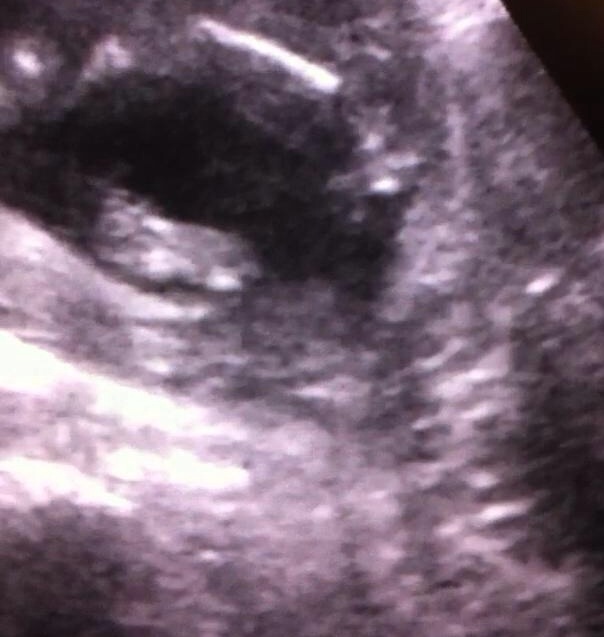

1st 2 pics were from 16 weeks scan everyone was unsure of those. ***NEW 3 pictures from 17 weeks scan

2 more picturesAttachment 25284Attachment 25285

looks boyish on all of them.

Boy